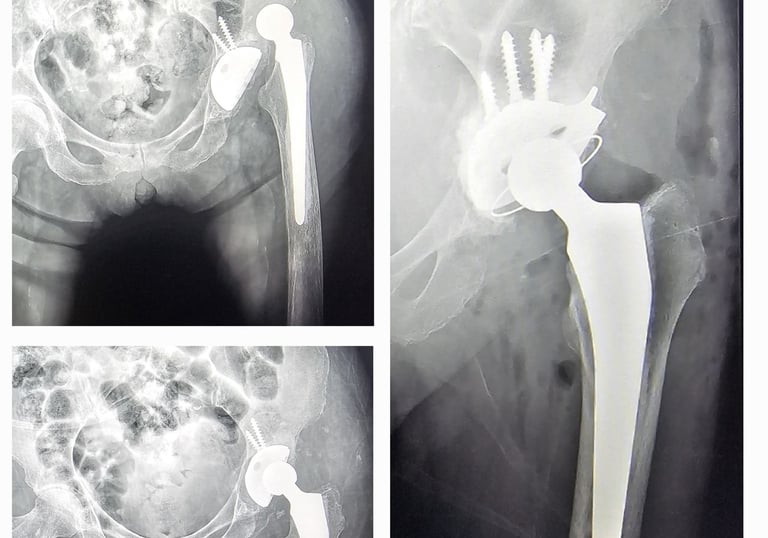

Cirugía de revisión de prótesis de cadera/rodilla: es una operación que se realiza cuando una prótesis ya no funciona adecuadamente, ya sea por aflojamiento, desgaste, infección o dolor persistente. En este procedimiento se retira la prótesis dañada y se coloca una nueva, con el objetivo de devolver estabilidad, movilidad y mejorar la calidad de vida del paciente.

Displasia del desarrollo de cadera: es una alteración en la formación de la articulación de la cadera que está presente desde el nacimiento. Puede provocar que la cabeza del fémur no encaje bien en el acetábulo (la cavidad de la pelvis), lo que con el tiempo ocasiona dolor, cojera y desgaste temprano de la articulación. Su detección y tratamiento oportuno permiten prevenir complicaciones y preservar la función de la cadera.

Secuelas de displasia de cadera

Prótesis de cadera y rodilla